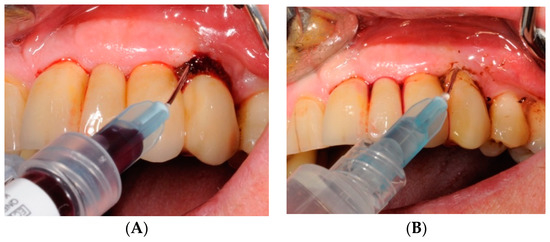

4.4. Study Protocol and Treatment

4.5. Test Substances and Administration